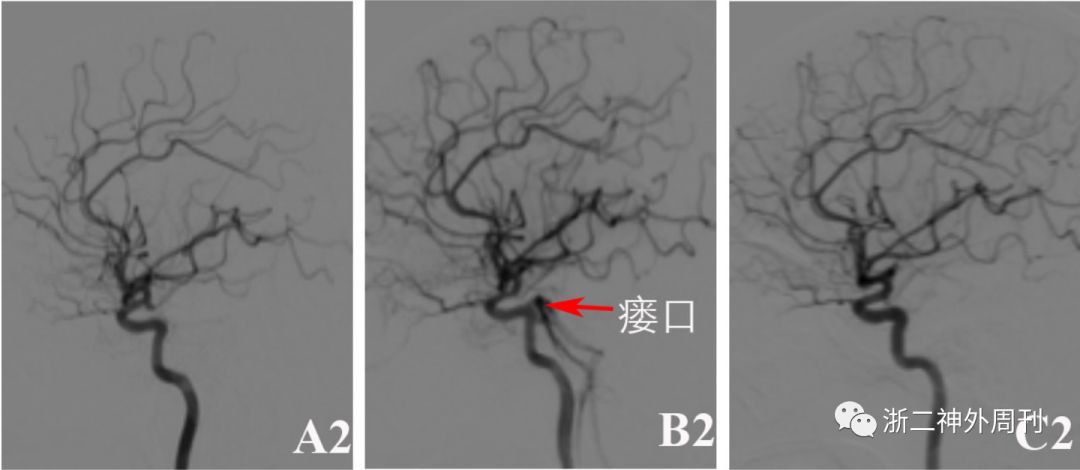

科室讨论,手术指证明确,建议开颅手术并告知手风险等,家属选择开颅夹闭手术。完善术前准备后,采用左侧眶上外侧入路开颅“左侧颈内动脉脉络膜前动脉段动脉瘤夹闭术”,手术过程顺利,术后患者恢复良好。无肢体活动障碍,无眼球结膜充血及颅内杂音等。术后4天常规复查DSA,提示动脉瘤夹闭满意,未见残留。但发现左侧海绵窦硬脑膜动静脉瘘,左侧脑膜垂体干动脉供血,瘘口位于左侧海绵窦后部,双侧岩下窦引流,静脉窦血流方向正常,无皮层静脉引流,诊断为I型左侧海绵窦后部硬脑膜动静脉瘘(图1B1-B3)。因无症状,建议患者密切随访观察,定期复查。期间患者一直无眼球结膜充血及颅内杂音等相关症状体征。8月后再次入院复查DSA,提示动脉瘤无复发,同时硬脑膜动静脉瘘消失(图1C1-C3)。

图1. A1-A3 术前DSA检查提示左侧颈内动脉脉络膜前动脉段动脉瘤;B1-B3:术后4天复查DSA提示动脉瘤夹闭满意,无残留;同时发现左侧海绵窦硬脑膜动静脉瘘,左侧脑膜垂体干动脉供血,瘘口位于左侧海绵窦后部,双侧岩下窦引流,静脉窦血流方向正常,无皮层静脉引流。C1-C3: 随访观察8月后复查DSA提示动脉瘤无复发,硬脑膜动静脉瘘消失。